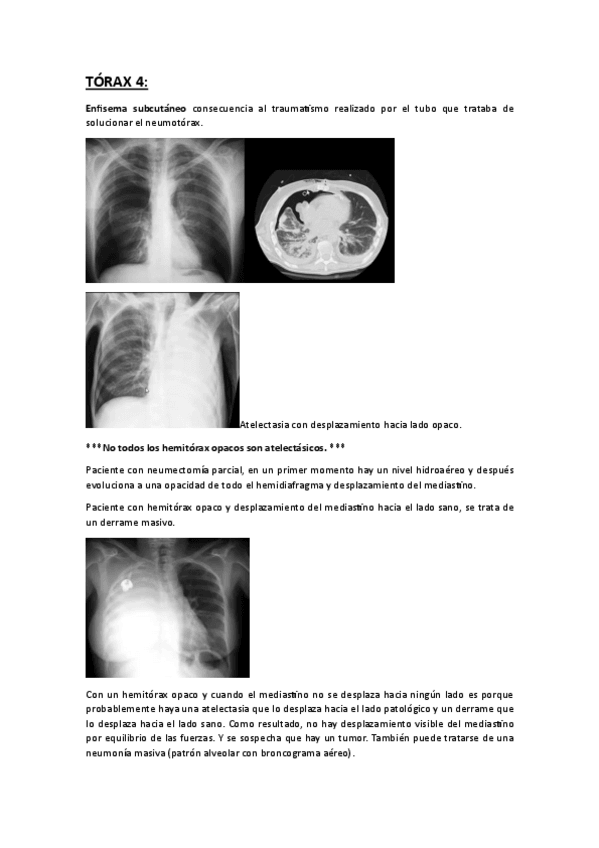

TÓRAX 2023-24

He publicado nuevos apuntes de 3º radiología y medicina nuclear: TÓRAX 2023-24

TORAX-4.pdf